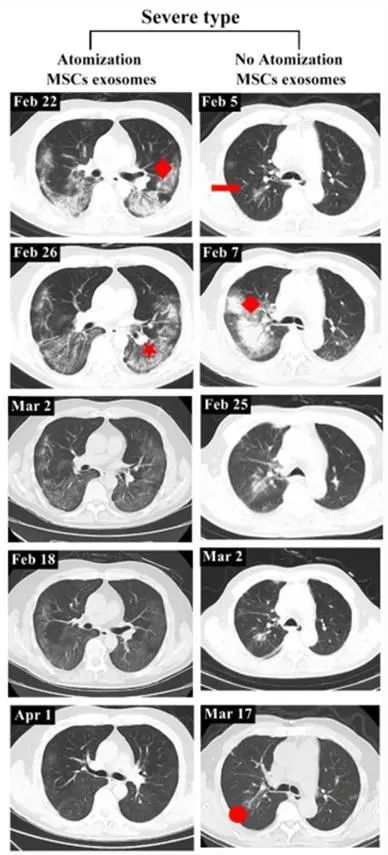

重度患者前后影像变化:以患者2为例,该患者从2020年2月27日开始接受外泌体治疗,3月18日,患者的CT扫描显示双肺病变明显吸收,病变密度消退。4月1日,该患者肺部病灶完全吸收。

而未接受外泌体治疗的重度患者,吸收肺病灶后仍然存在纤维脐带阴影。

▲左:患者2;右:无外泌体雾化治疗的重度病例